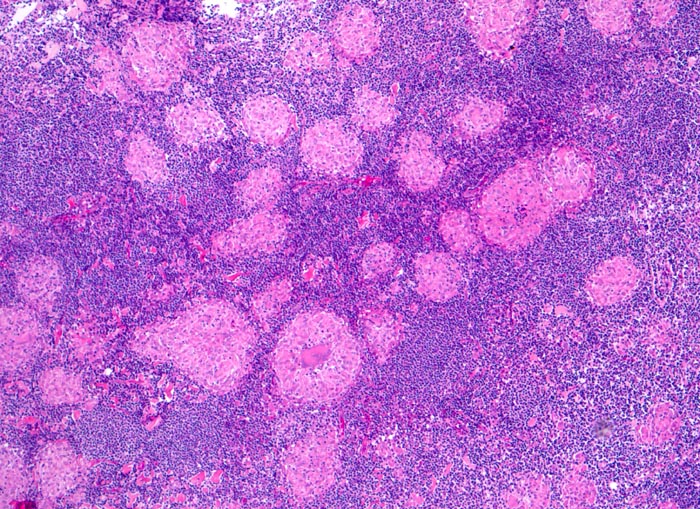

Sarkoidosegranulome bestehen aus Epitheloidzellen mit einem peripheren Lymphozytensaum. Mehrkernige Riesenzellen, meistens solche vom Langhans-Typ mit hufeisenförmig angeordneten Kernen und Asteroidkörperchen (> 4173) können zusätzlich vorhanden sein. Diese Granulome enthalten meist keine Nekroseherde (=produktives Granulom). Man findet diesen Granulomtyp hauptsächlich in Lymphknoten, aber auch in inneren Organen und in der Haut. Die Sarkoidosegranulome zeigen in späteren Stadien eine charakteristische perigranulomatöse und die Granulome septierend unterteilende Fibrose (> 4015).

Morphologische Merkmale:

• Wenig erhaltenes Lymphknotengewebe (blau).

• Konfluierende Granulome aus grossleibigen Epitheloidzellen.

• Wenige mehrkernige Riesenzellen.

• Kleinere Nekroseareale im Zentrum grösserer Granulome. (Die Nekrosen sind untypisch für die Sarkoidose, können aber bei grossen Granulomen gelegentlich vorkommen).

• Perigranulomatöse Fibrose. Das sollte der Kliniker dem Pathologen mitteilen: